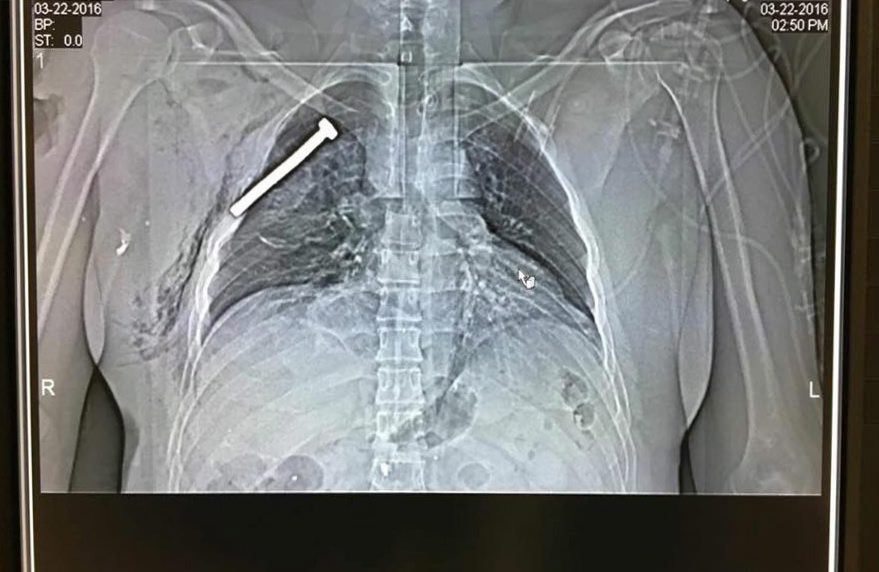

Μία ακτινογραφία ενός εκ των δεκάδων τραυματιών από τις βομβιστικές επιθέσεις στη βελγική πρωτεύουσα επιβεβαιώνει με ανατριχιαστικό τρόπο την αποκάλυψη των αρχών ασφαλείας, ότι οι τρομοκράτες είχαν βάλει καρφιά και βίδες στις βόμβες, προκειμένου να σκοτώσουν περισσότερους ανθρώπους.

Τη φωτογραφία από την ακτινογραφία δημοσίευσε το πρακτορείο ΕPA. Είναι ενός τραυματία, που μεταφέρθηκε σε στρατιωτικό νοσοκομείο στα βόρεια των Βρυξελλών. Σε αυτή φαίνεται μία βίδα ή καρφί, στο στήθος του ασθενούς.